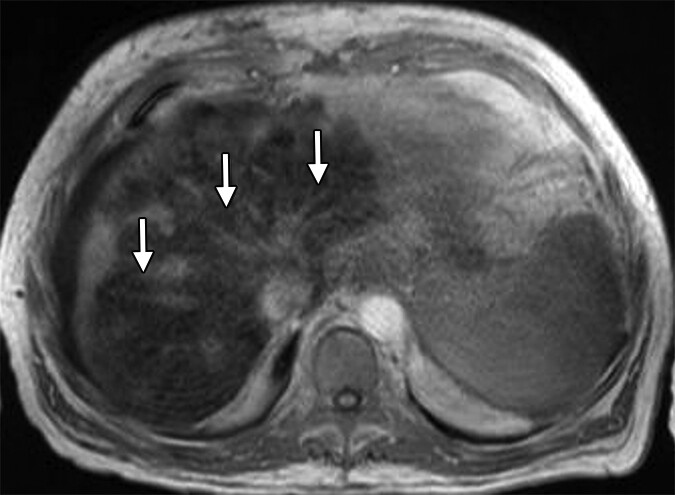

For 26 years as a hepatologist, I've reviewed thousands of liver scans like the one you see here. The arrows point to what many doctors consider an "expected finding" in patients over 50—early signs of fatty infiltration with fibrotic changes.